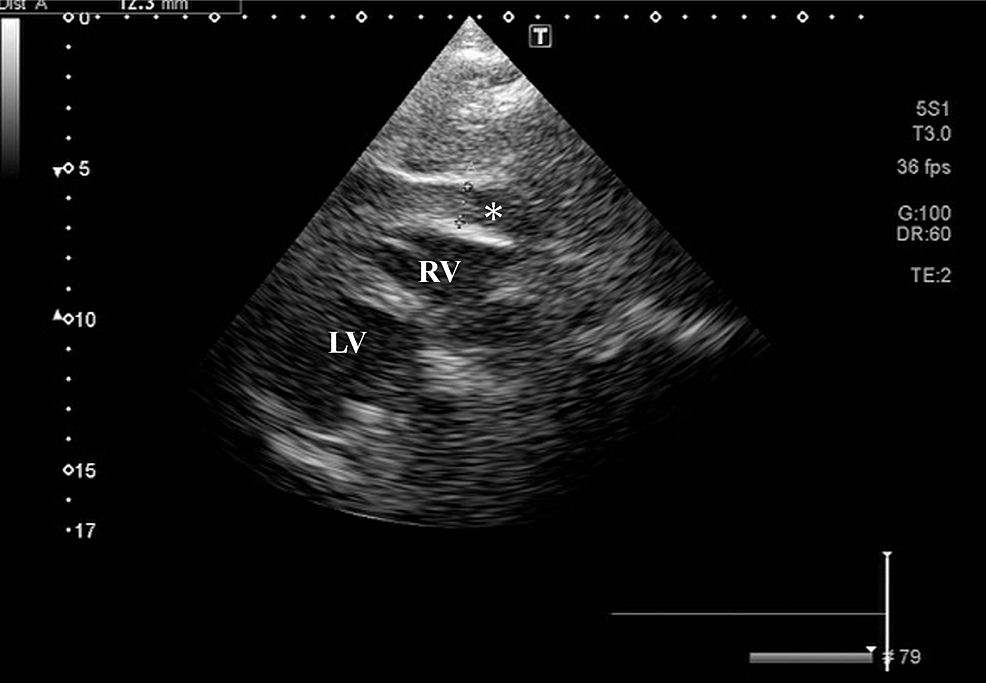

Case Report Free Wall Rupture . Without cardiac surgery, 94% of patients with left ventricular free wall rupture (lvfwr) due to tcm die. Pericardiocentesis revealed hemopericardium, and multidetector computed tomography angiography showed left ventricular free wall rupture. Here we present a case of a patient who suffered a left ventricular free wall rupture as a mechanical complication of myocardial. Through our case we highlight the. Left ventricular (lv) free wall ruptures (lvfwrs) of myocardial infarctions (mis) are still one of the most fatal mechanical complications. We are presenting the case of a 58 years old male with left ventricular free wall rupture occurred.

We are presenting the case of a 58 years old male with left ventricular free wall rupture occurred. Pericardiocentesis revealed hemopericardium, and multidetector computed tomography angiography showed left ventricular free wall rupture. Left ventricular (lv) free wall ruptures (lvfwrs) of myocardial infarctions (mis) are still one of the most fatal mechanical complications. Here we present a case of a patient who suffered a left ventricular free wall rupture as a mechanical complication of myocardial. Without cardiac surgery, 94% of patients with left ventricular free wall rupture (lvfwr) due to tcm die. Through our case we highlight the.

Case Report Free Wall Rupture Left ventricular (lv) free wall ruptures (lvfwrs) of myocardial infarctions (mis) are still one of the most fatal mechanical complications. We are presenting the case of a 58 years old male with left ventricular free wall rupture occurred. Here we present a case of a patient who suffered a left ventricular free wall rupture as a mechanical complication of myocardial. Without cardiac surgery, 94% of patients with left ventricular free wall rupture (lvfwr) due to tcm die. Through our case we highlight the. Left ventricular (lv) free wall ruptures (lvfwrs) of myocardial infarctions (mis) are still one of the most fatal mechanical complications. Pericardiocentesis revealed hemopericardium, and multidetector computed tomography angiography showed left ventricular free wall rupture.